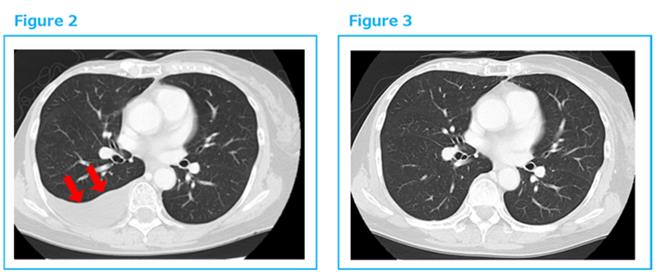

2014年底出現(xiàn)胸水,穿刺診斷復(fù)發(fā)。于是2015年1月再開始αβT細(xì)胞治療,每2周1次共6次,之后每個(gè)月1次。到2016年3月胸水完全消失。